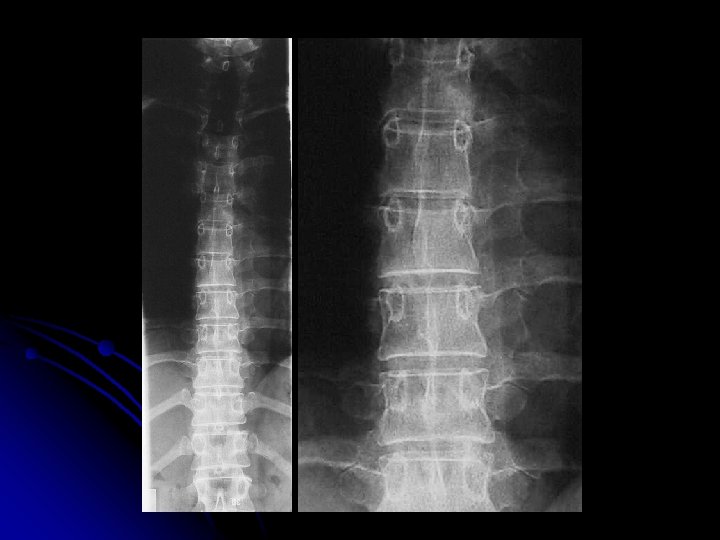

Rachis lombaire de face l Critères de réussite : l En haut : T 11 -T 12 l En bas: la symphyse pubienne et une partie des coxofémorales l Disques L 1 -L 2 à L 4 -L 5: enfilés.

l Statique rachidienne, l Morphologie: l des corps vertébraux, l des arcs postérieurs, et l’espace inter-arcual l Hauteur des espaces intervertébraux l Bords externes des psoas l Anomalie transitionnelle

Rachis lombaire de profil

l Statique rachidienne l Morphologie et structure des corps vertébraux, l Hauteur des espaces inter-vertébraux l Morphologie des arcs postérieurs